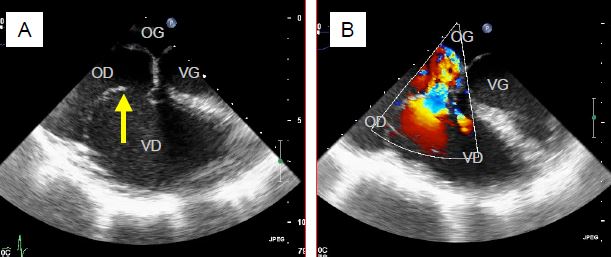

• Dégénérescence myxoïde (Barlow) et bascule de feuillet (flail leaflet): en général associée à un prolapsus mitral (Vidéos).

Vidéo: Basculement du feuillet postérieur occasionnant une insuffisance sévère.

Vidéo: Insuffisance tricuspidienne massive au flux couleur dans le même cas.